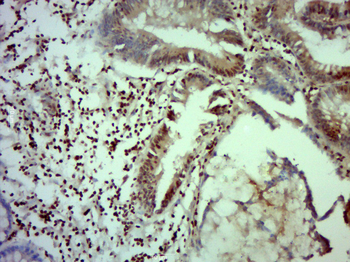

Antibody used in IHC on Human Intestine at 4.0-8.0 ug/ml.